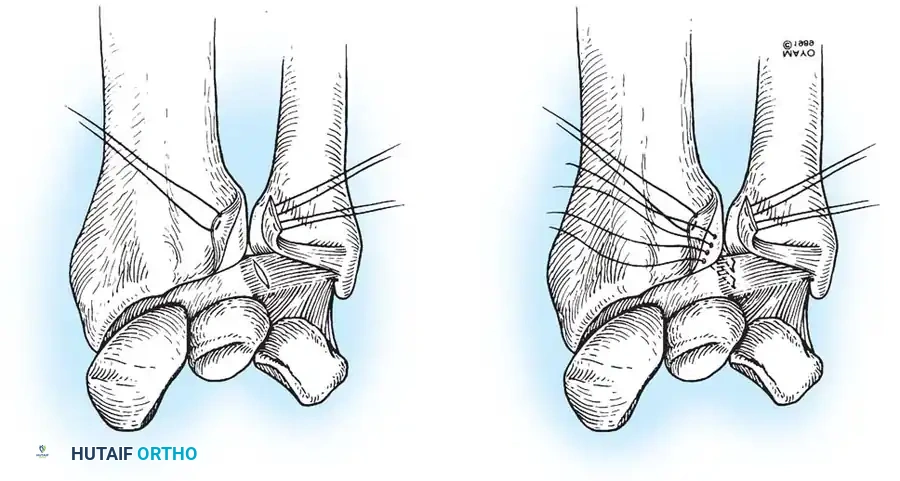

If the DRUJ remains unstable after soft tissue repair, temporary transarticular K-wire fixation may be necessary to protect the repair during the initial healing phase.

Radiographic confirmation of temporary transarticular K-wire fixation stabilizing the DRUJ following complex TFCC repair.

Chronic Instability and TFCC Reconstruction

In chronic settings where the TFCC is irreparable, anatomic ligament reconstruction using a tendon autograft (e.g., palmaris longus) is indicated. The graft is routed through the distal radius and ulnar fovea to recreate the dorsal and volar radioulnar ligaments.

Tendon graft routing through osseous tunnels in the radius and ulna for anatomic reconstruction of the DRUJ ligaments.